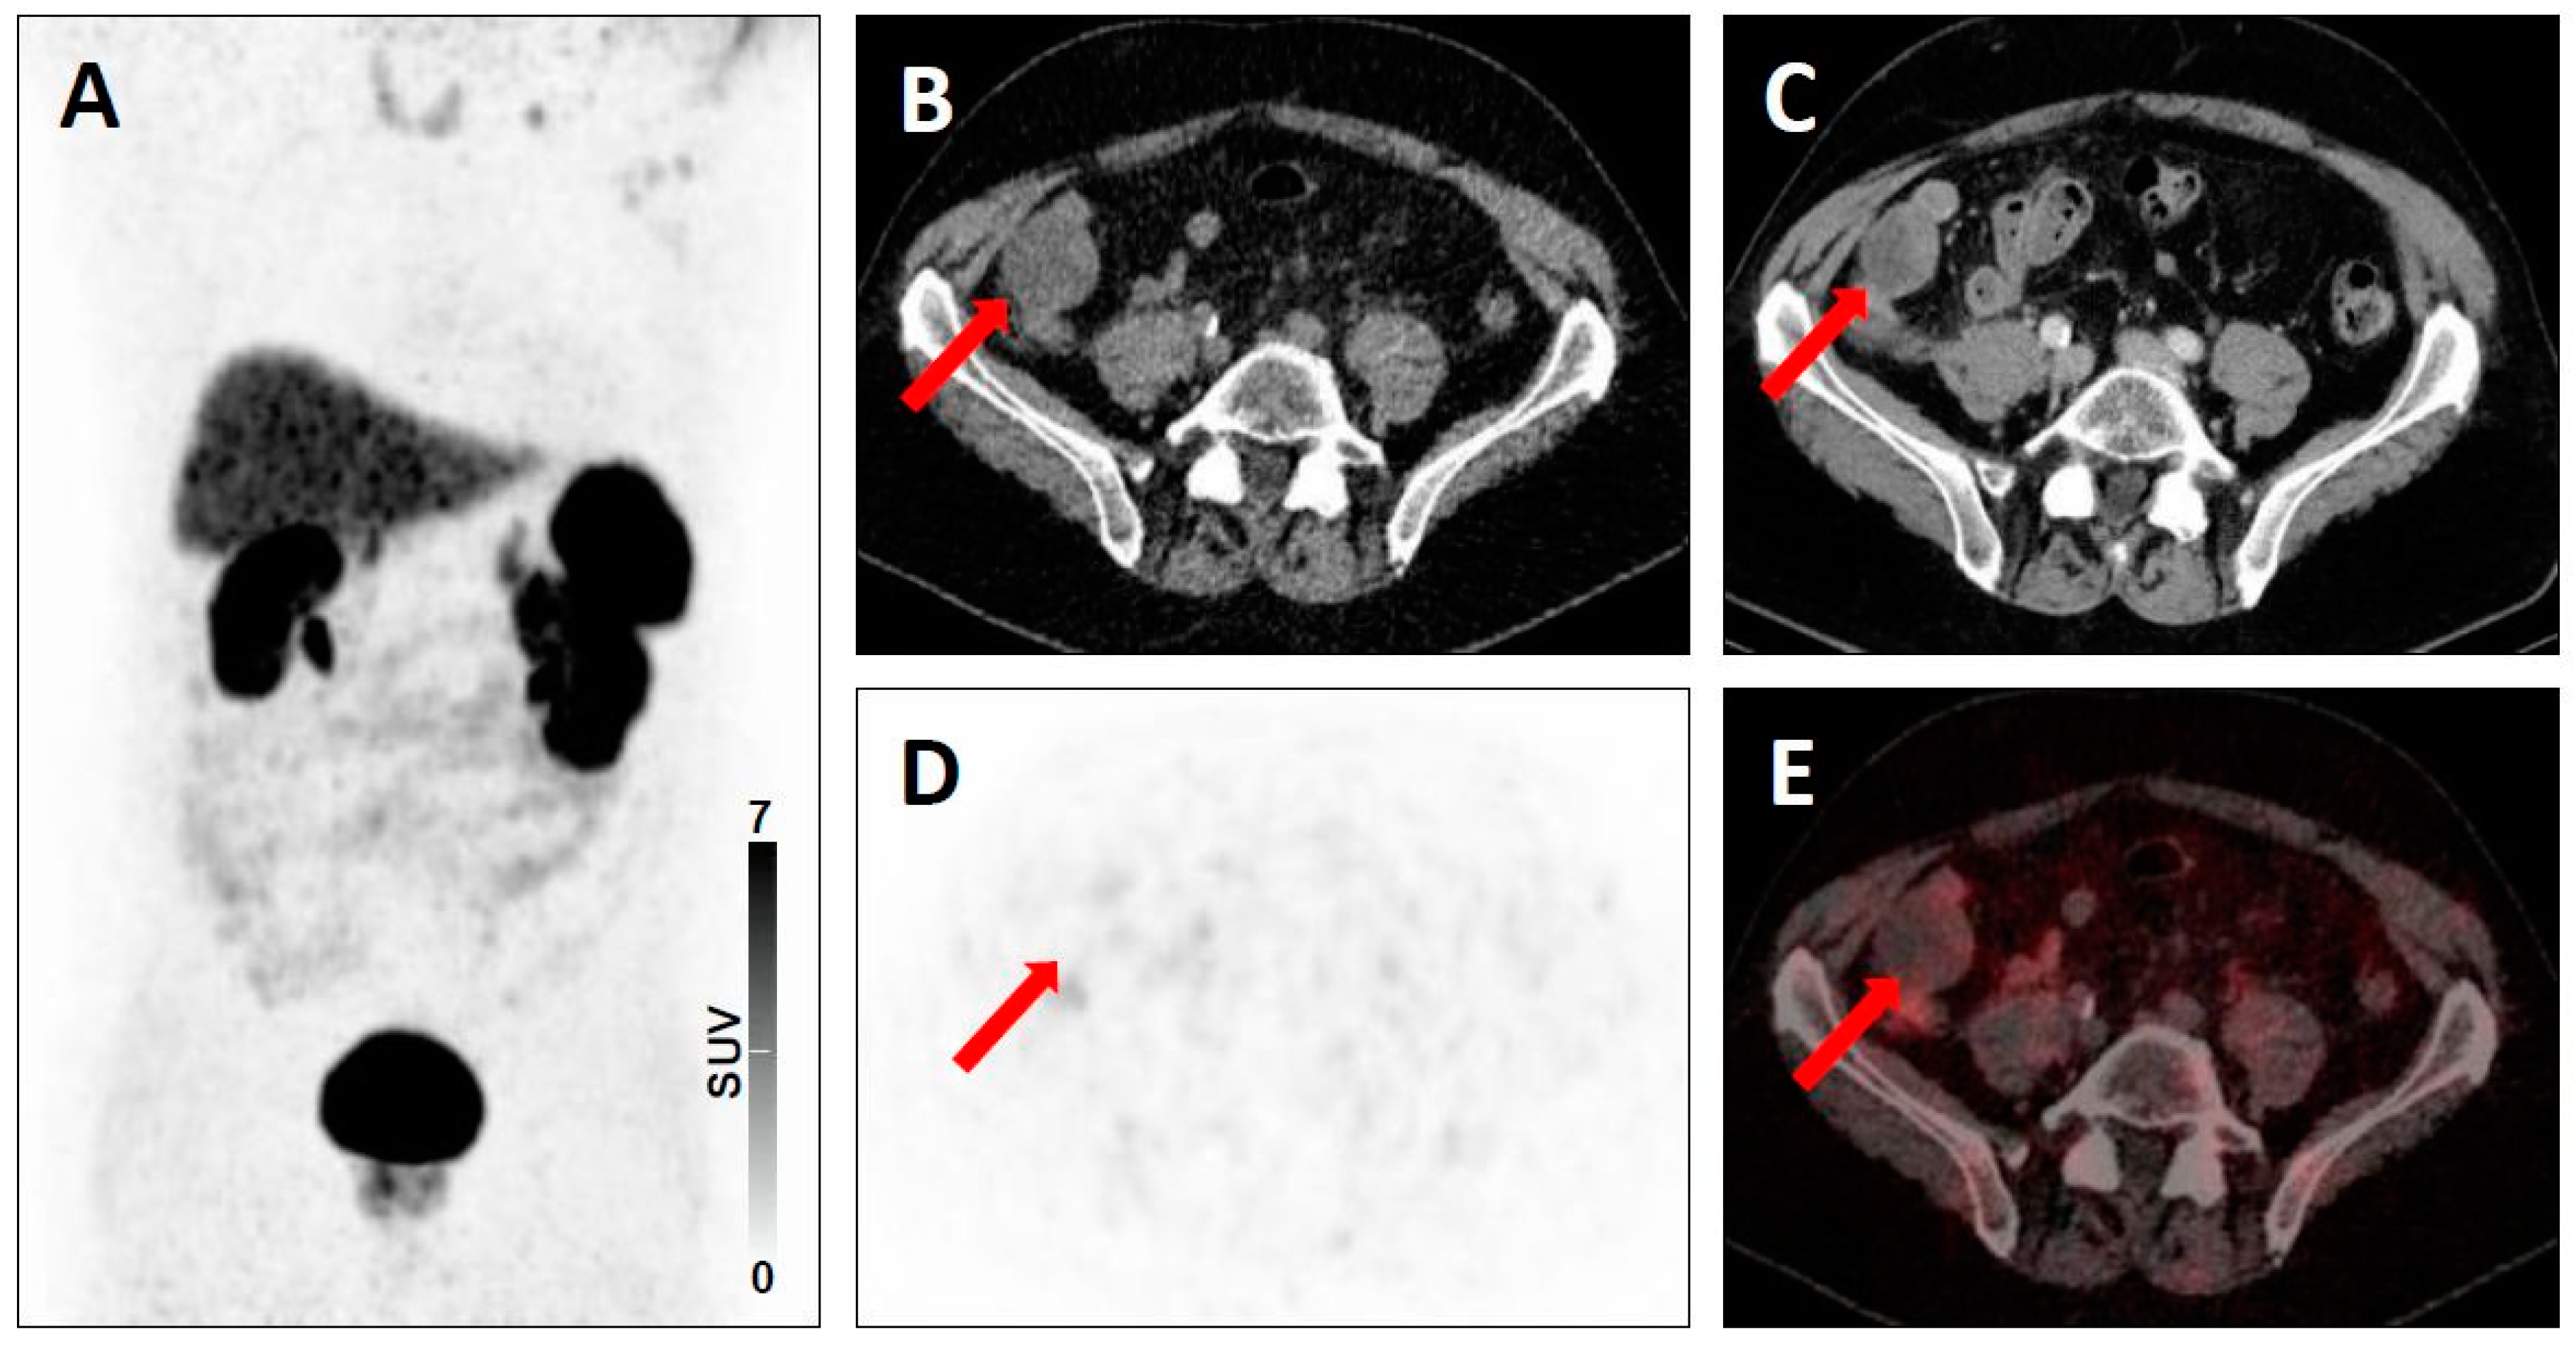

| 3B | - Low-level uptake in a rib with lack of anatomic correlate [20] | - Low level-uptake in the iliac bone with lack of anatomic correlate [19] | |